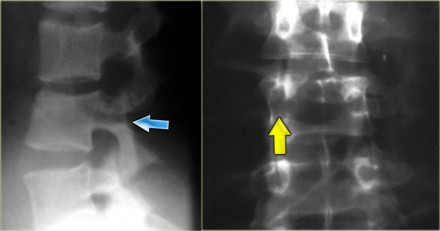

On the left images of a 31 year old male.

He was working on a roof, fell approximately 5 meters landing on his feet.

He complained of pain in left lower extremity and lower back.

On the x-ray there is a hyperflexion injury of L1 with involvement of the anterior column and possible involvement of the middle column.

The sagittal reconstructions of the CT demonstrate that the posterior part of the vertebral body is of normal height, but there is some involvement of the posterior part of the vertebral body.